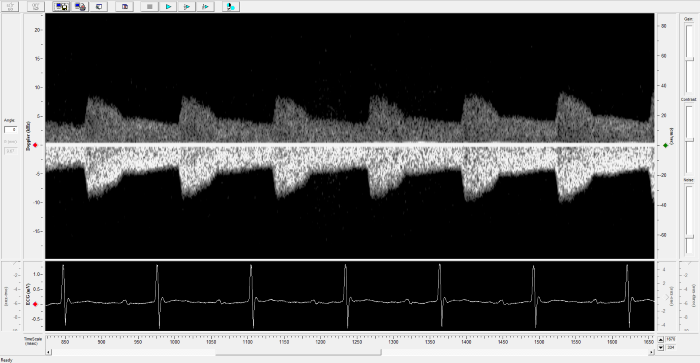

Imaging gallery - Doppler Flow Velocity System

Renal Flow. Image Credit: Scintica Instrumentation Inc.